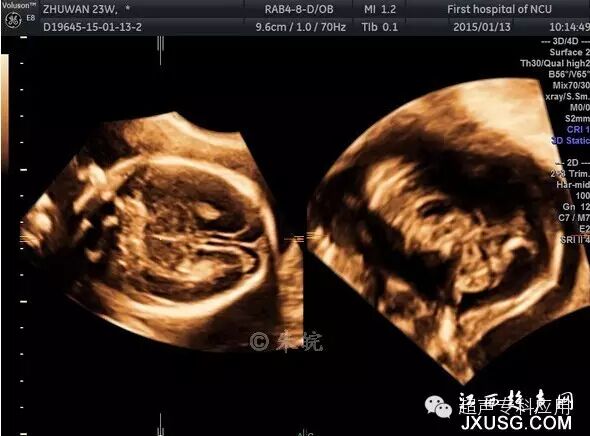

1.1 表面结构的成像 这是三维超声最初在胎儿显像的应用。早孕期可显示整个胎儿的形态以及头颅、腹壁、四肢等;中孕期则能显示胎儿头面部、手指(脚趾)等相对细小的结构。这些表面结构的三维图像,客观逼真,一旦存在胎儿体表的畸形,如唇裂、脑膨出、脊柱裂、脐膨出、腹裂、肢体或手脚畸形,三维成像能够让孕妇及家属一目了然,让产科医生或儿科医生更结合实际情况进行咨询,方便选择下一步的处理方案。虽然三维超声对体表畸形的诊断可能并不比二维超声提供更多信息,这些体表畸形可能在二维声像图上也较容易显示,但孕妇及家属却不理解二维图像,难以想象畸形外观如何、有多严重。为了更人性化的服务,目前,也有不少医院或产院对孕妇提供“胎儿照相”;四维超声观看胎儿运动并录像,以留作纪念。三维表面成像的重要条件是感兴趣区域前方一定要有足够的羊水,而且不能被肢体、脐带等遮挡。羊水过少或晚孕期胎儿充满官腔时,三维表面成像则有较大困难。

1.2 骨骼系统检查 与二维超声相比,三维超声的透明成像或最大模式成像可清晰显示骨骼系统,包括颅骨、脊柱、肋骨及四肢骨骼,这对观察骨骼的发育、有无存在畸形帮助很大。有文献报道显示,二维超声发现的长骨短小、手指短粗、异常骨骼钙化、胸廓狭小、肋骨异常、前额突出、面部异常等现象,若增加三维超声的观察,所有病例的畸形状况均可显示得更形象、清晰。有时,一些二维超声难以呈现的结构,三维超声却能显现。最常用的是脊柱三维成像,可显示从颈椎至骶尾椎整条脊柱,计算椎体椎弓的数目,计算双侧肋骨的数目,发现半椎体、脊柱侧突、肋骨缺失或融合等异常情况。还有,颅骨颅缝的检查,发现颅缝早闭,对小头畸形的诊断无疑又提高了一步。

胎儿脊柱三维超声成像-最大模式